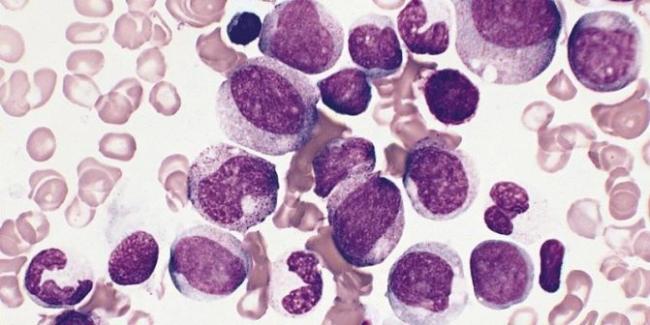

Для начала вспомним, что такое эозинофилы. Они являются видом лейкоцитов, образующихся в костном мозге.

Рак крови

При опухолях крови может быть повышение эозинофилов из-за усиленного их образования в костном мозге. При лейкозах характерно медленное, но устойчивое увеличение клеток до 60-70%, а их уменьшение возможно только при применении противоопухолевых препаратов.